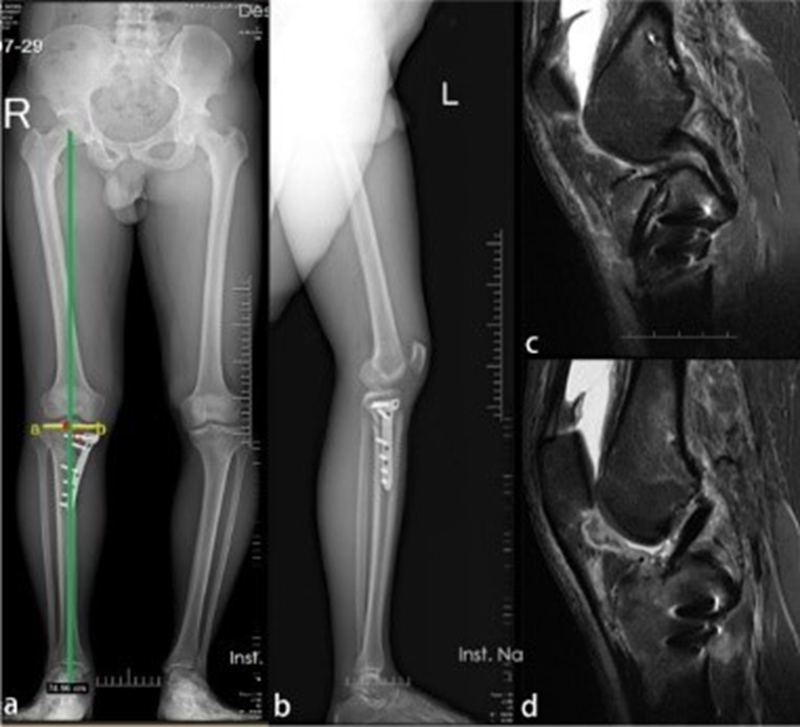

Deng等人报道一例ACLR联合OWHTO治疗膝内翻合并ACL撕裂的病例。一名27岁男性因运动损伤入院,诊断为与内翻畸形和胫骨后倾过大相关的ACL撕裂。之后,该患者接受了ACLR联合OWHTO以纠正内翻畸形和过大的胫骨后倾角[7]

图5